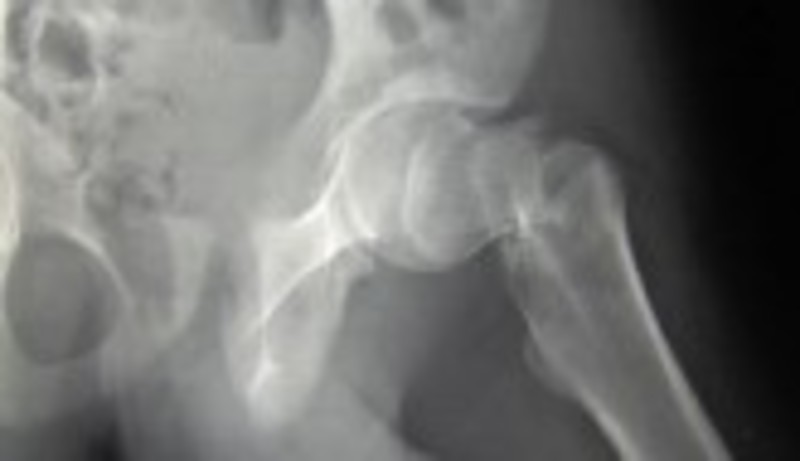

Una de cada cinco mujeres que sufre una fractura de cadera muere un año después de haber sufrido el accidente que le causó este daño, según señala un estudio observacional sobre la osteoporosis realizado con datos de más de 210.000 pacientes de más de 65 años.

La investigación 'Real World Effectiveness Study', publicada en 'Osteoporosis Internacional', ha concluido con que una de cada cinco mujeres que sufre fractura de cadera muere al año. Este estudio tiene en cuenta que en el caso de las mujeres mayores de 45 años la fractura osteoporótica, y especialmente la de cadera, provoca al año más días de hospitalización que los generados por patologías como el infarto de miocardio, el cáncer de pulmón o la diabetes.

Asimismo, recalca que las fracturas osteoporóticas y las de cadera, en concreto, constituyen un problema de salud pública responsable de un aumento de la mortalidad, discapacidad funcional y costes adicionales de Atención Primaria.